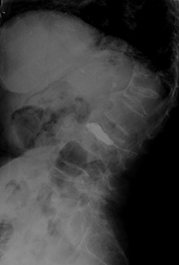

因:“腰椎骨折椎体成形术后2天”入院

患者因“脑卒中后遗症”在我中心康复治疗,于4月27日行走时滑倒腰部跌伤,当时即感疼痛,活动受限,到当地医院就诊,经CT等检查后,诊断为L3骨折,予卧床休息、口服活血化瘀及镇痛等对症治疗,患者自觉症状无改善,于6月03日在上级医院行椎体成形手术,2014年6月04日再次转入我中心继续康复治疗。患者入院时腰背部疼痛明显改善,并可下床活动。

神清,精神可,轮椅推入病房,精神略显紧张,发育正常,营养中等,呼吸平稳,查体合作,言语清晰,对答切题。全身皮肤粘膜无黄染,无皮疹、无淤斑、淤点,毛发分布正常,皮温正常、皮肤弹性正常,无肝掌。浅表淋巴结未及肿大。头颅大小正常,无畸形,眼睑无水肿,结膜无充血,眼球正常,无运动障碍,巩膜无黄染,角膜正常,双侧瞳孔等大等圆7.5px,对光反射正常。左侧鼻唇沟浅,左侧口角下垂,左侧额纹消失,耳廓正常,外耳道无脓性分泌物,乳突无压痛,双侧听力正常。鼻外形正常,鼻道畅,鼻中隔无偏曲,鼻旁窦无压痛。口唇红润无绀,口腔粘膜正常,舌正常,伸舌居中,牙龈无肿胀出血,咽无充血,双侧扁桃体未见肿大,声音正常。颈软,无抵抗,脑膜刺激征阴性,气管居中,颈静脉无充盈,双侧甲状腺未及肿大,无压痛。胸廓无明显畸形,乳头对称,双侧呼吸运动对称,语颤相等,叩诊清音,双肺呼吸音粗,未及明显干湿啰音。心前区未见异常隆起,心尖搏动位于左第5肋锁骨中线内12.5px,未及震颤,心相对浊音界正常。心率80次/分,律齐,各瓣膜听诊区未闻及病理性杂音。未及水冲脉、股动脉枪击音。腹平,未见腹壁静脉曲张,未见肠型蠕动波,腹软,无压痛、反跳痛,肝脾肋下未及,肾未触及,全腹未触及包块,肝肾区无叩痛,移动性浊音阴性,肠鸣音正常,5次/分。脊柱胸腰段后凸畸形,活动度轻度受限,棘突无明显叩痛,双下肢无水肿。四肢肌力正常,关节无畸形。双下肢感觉正常。

入院诊断:(1)腰椎骨折术后